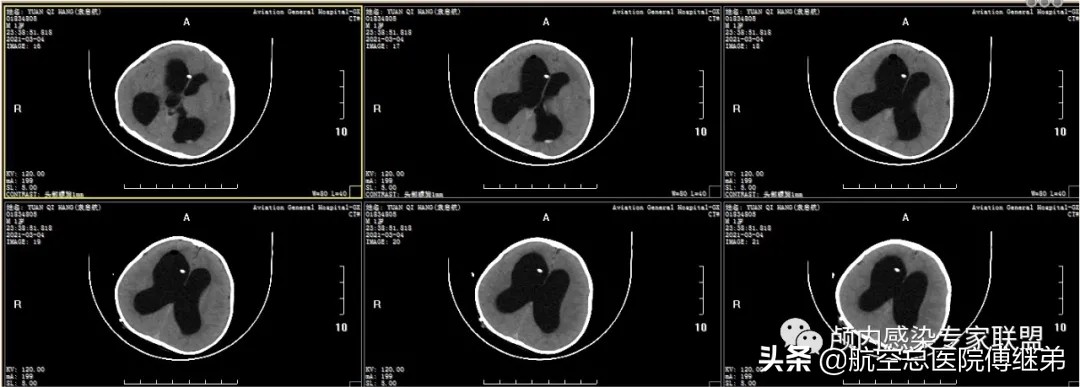

入院后完善相关检查,于2021-03-04在全麻下行脑室腹腔外引流术+原储液囊取出术。术后复查颅脑CT脑室引流管位置可(图六),术后早期引*脑流**脊液为淡黄色,患儿状态逐渐改善(图七)。

图六 术后复查颅脑CT脑室引流管位置可